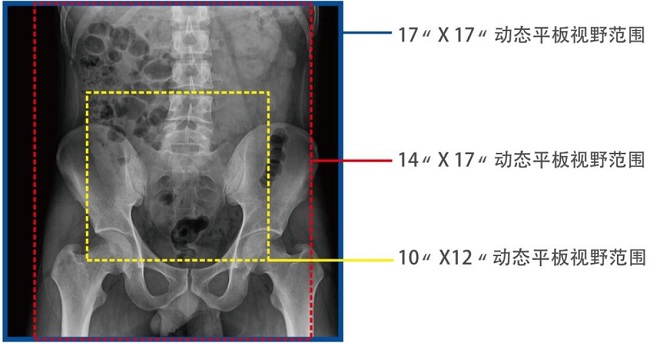

17*17英寸的超高清像素動態平板探測器,更大的視野范圍,能對胸部腹部等部位實現大范圍全覆蓋,動靜態之間無感切換。透視檢查無須對患者重新定位便可觀察到足夠大的人體器官組織,避免漏診誤診。

大尺寸動態平板技術,覆蓋檢查面積范圍廣,輕松實現胃十二指腸等大面積造影,無需移動即可觀看整個動態過程,避免噪點對圖像的影響。